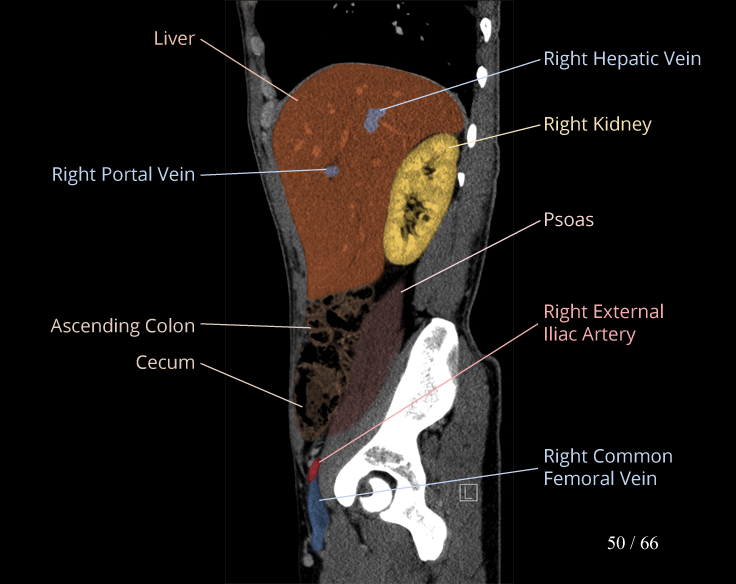

Body

Covers abdominal CT anatomy.